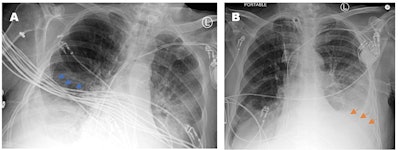

Two portable chest x-rays from a patient acquired at different times of the same day. The rotated and mispositioned film (A) cuts off the left cardiophrenic angle, which ended up concealing a large left-sided pleural effusion (orange arrows). The cardiac silhouette appears exaggerated and the EKG wires (blue arrows) severely obscure evaluation of the right lower chest and the right lower lobe airspace opacities. Image courtesy of Cureus.Two portable chest x-rays from a patient acquired at different times of the same day. The rotated and mispositioned film (A) cuts off the left cardiophrenic angle, which ended up concealing a large left-sided pleural effusion (orange arrows). The cardiac silhouette appears exaggerated and the EKG wires (blue arrows) severely obscure evaluation of the right lower chest and the right lower lobe airspace opacities. Image courtesy of Cureus.

Out of the 500 images evaluated, 231 were problematic (46.2%). Of these, 28% were from the day shift, 24% from the evening shift, and 48% were from the night shift, according to the findings.

In addition, 43.5% of the problematic films with a repeat portable chest x-ray within one week showed there were technical problems impacting the ability to detect pathology. Key issues that led to poor image quality included improper patient positioning, foreign objects covering anatomy, and variances in technologists' training, the authors wrote.